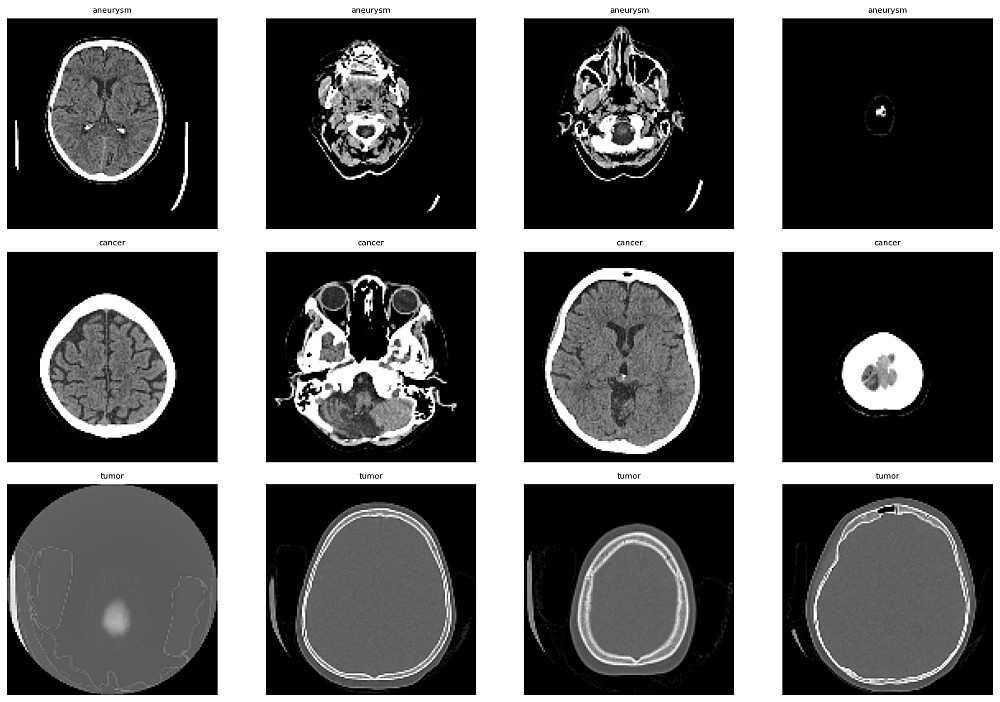

3-تصنيف الصور CNN

4-كشف الأشياء ومحتويات الصور والكاميرات copmuter vision , object detection